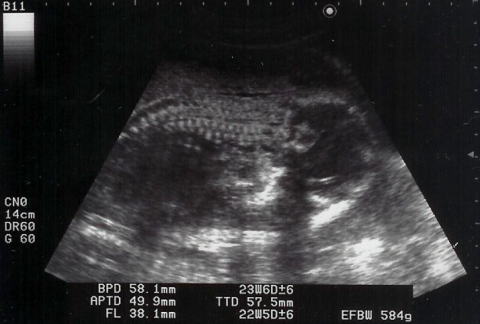

これも、うつ伏せで背骨クッキリの写真